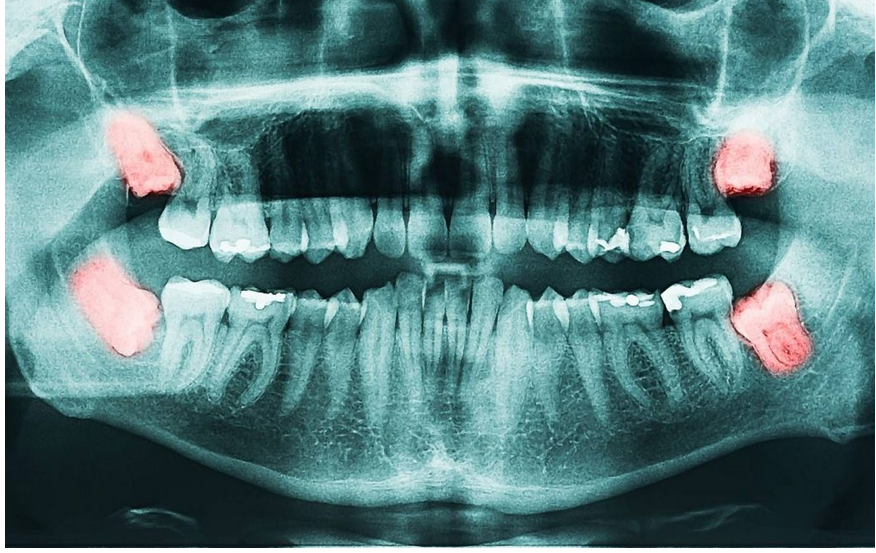

Odluka o vađenju umnjaka ne donosi se olako. Stomatolog procjenjuje položaj zuba, stanje okolnih tkiva i opšte zdravlje pacijenta. Rendgenski snimak vilice, najčešće ortopan, pruža detaljan uvid u to da li zub ima prostora za pravilan rast ili predstavlja rizik za susjedne zube. Najčešće indikacije za vađenje uključuju učestale upale, impaktirane zube zarobljene u kosti, naginjanje prema sedmici, dubok karijes koji se ne može adekvatno liječiti ili stvaranje parodontalnih džepova.